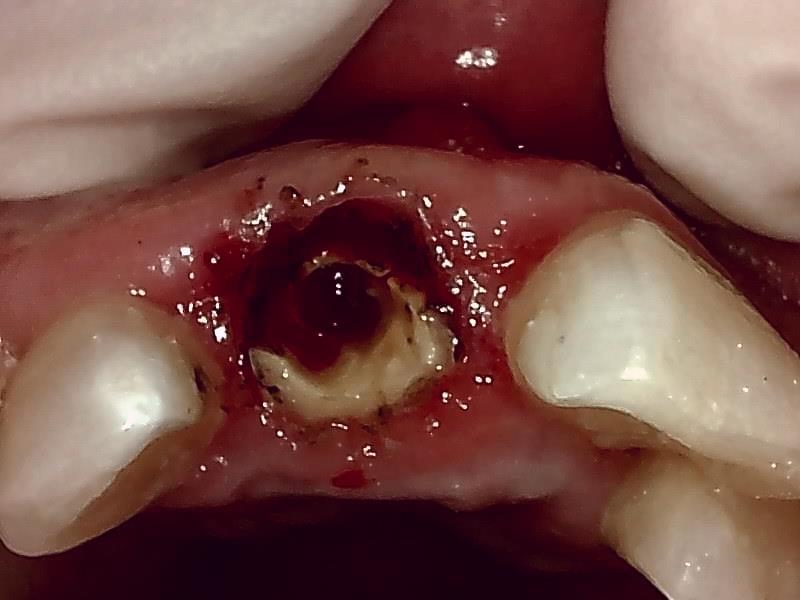

抜歯窩の状態

自家骨移植 GBR を施す。理想的な顎堤に築造する。